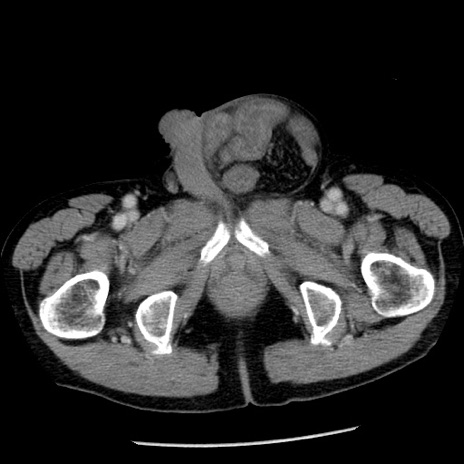

症例26(横断像)

【症例】80歳代男性

【主訴】嘔吐

【現病歴】昨晩2回嘔吐あり、今朝になっても嘔吐あり。来院。

【既往歴】胃潰瘍

【身体所見】意識清明、BT 37.6℃、BP 166/95mmHg、HR 100bpm、SpO2 97%、腹部:平坦・軟、腸蠕動音聴取良好、圧痛なし。

【データ】WBC 21900、CRP 1.46